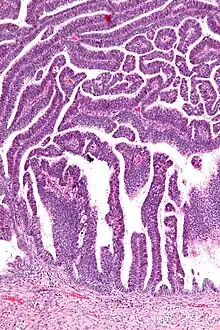

The name of the lesion describes it microscopic appearance. It has nipple-like structures with fibrovascular cores (papillae) that are long in relation to their width (villus-like), which are covered with a glandular pseudostratified columnar epithelium.

Micrograph of a villoglandular adenocarcinoma the cervix. H&E stain.

Intermediate magnification